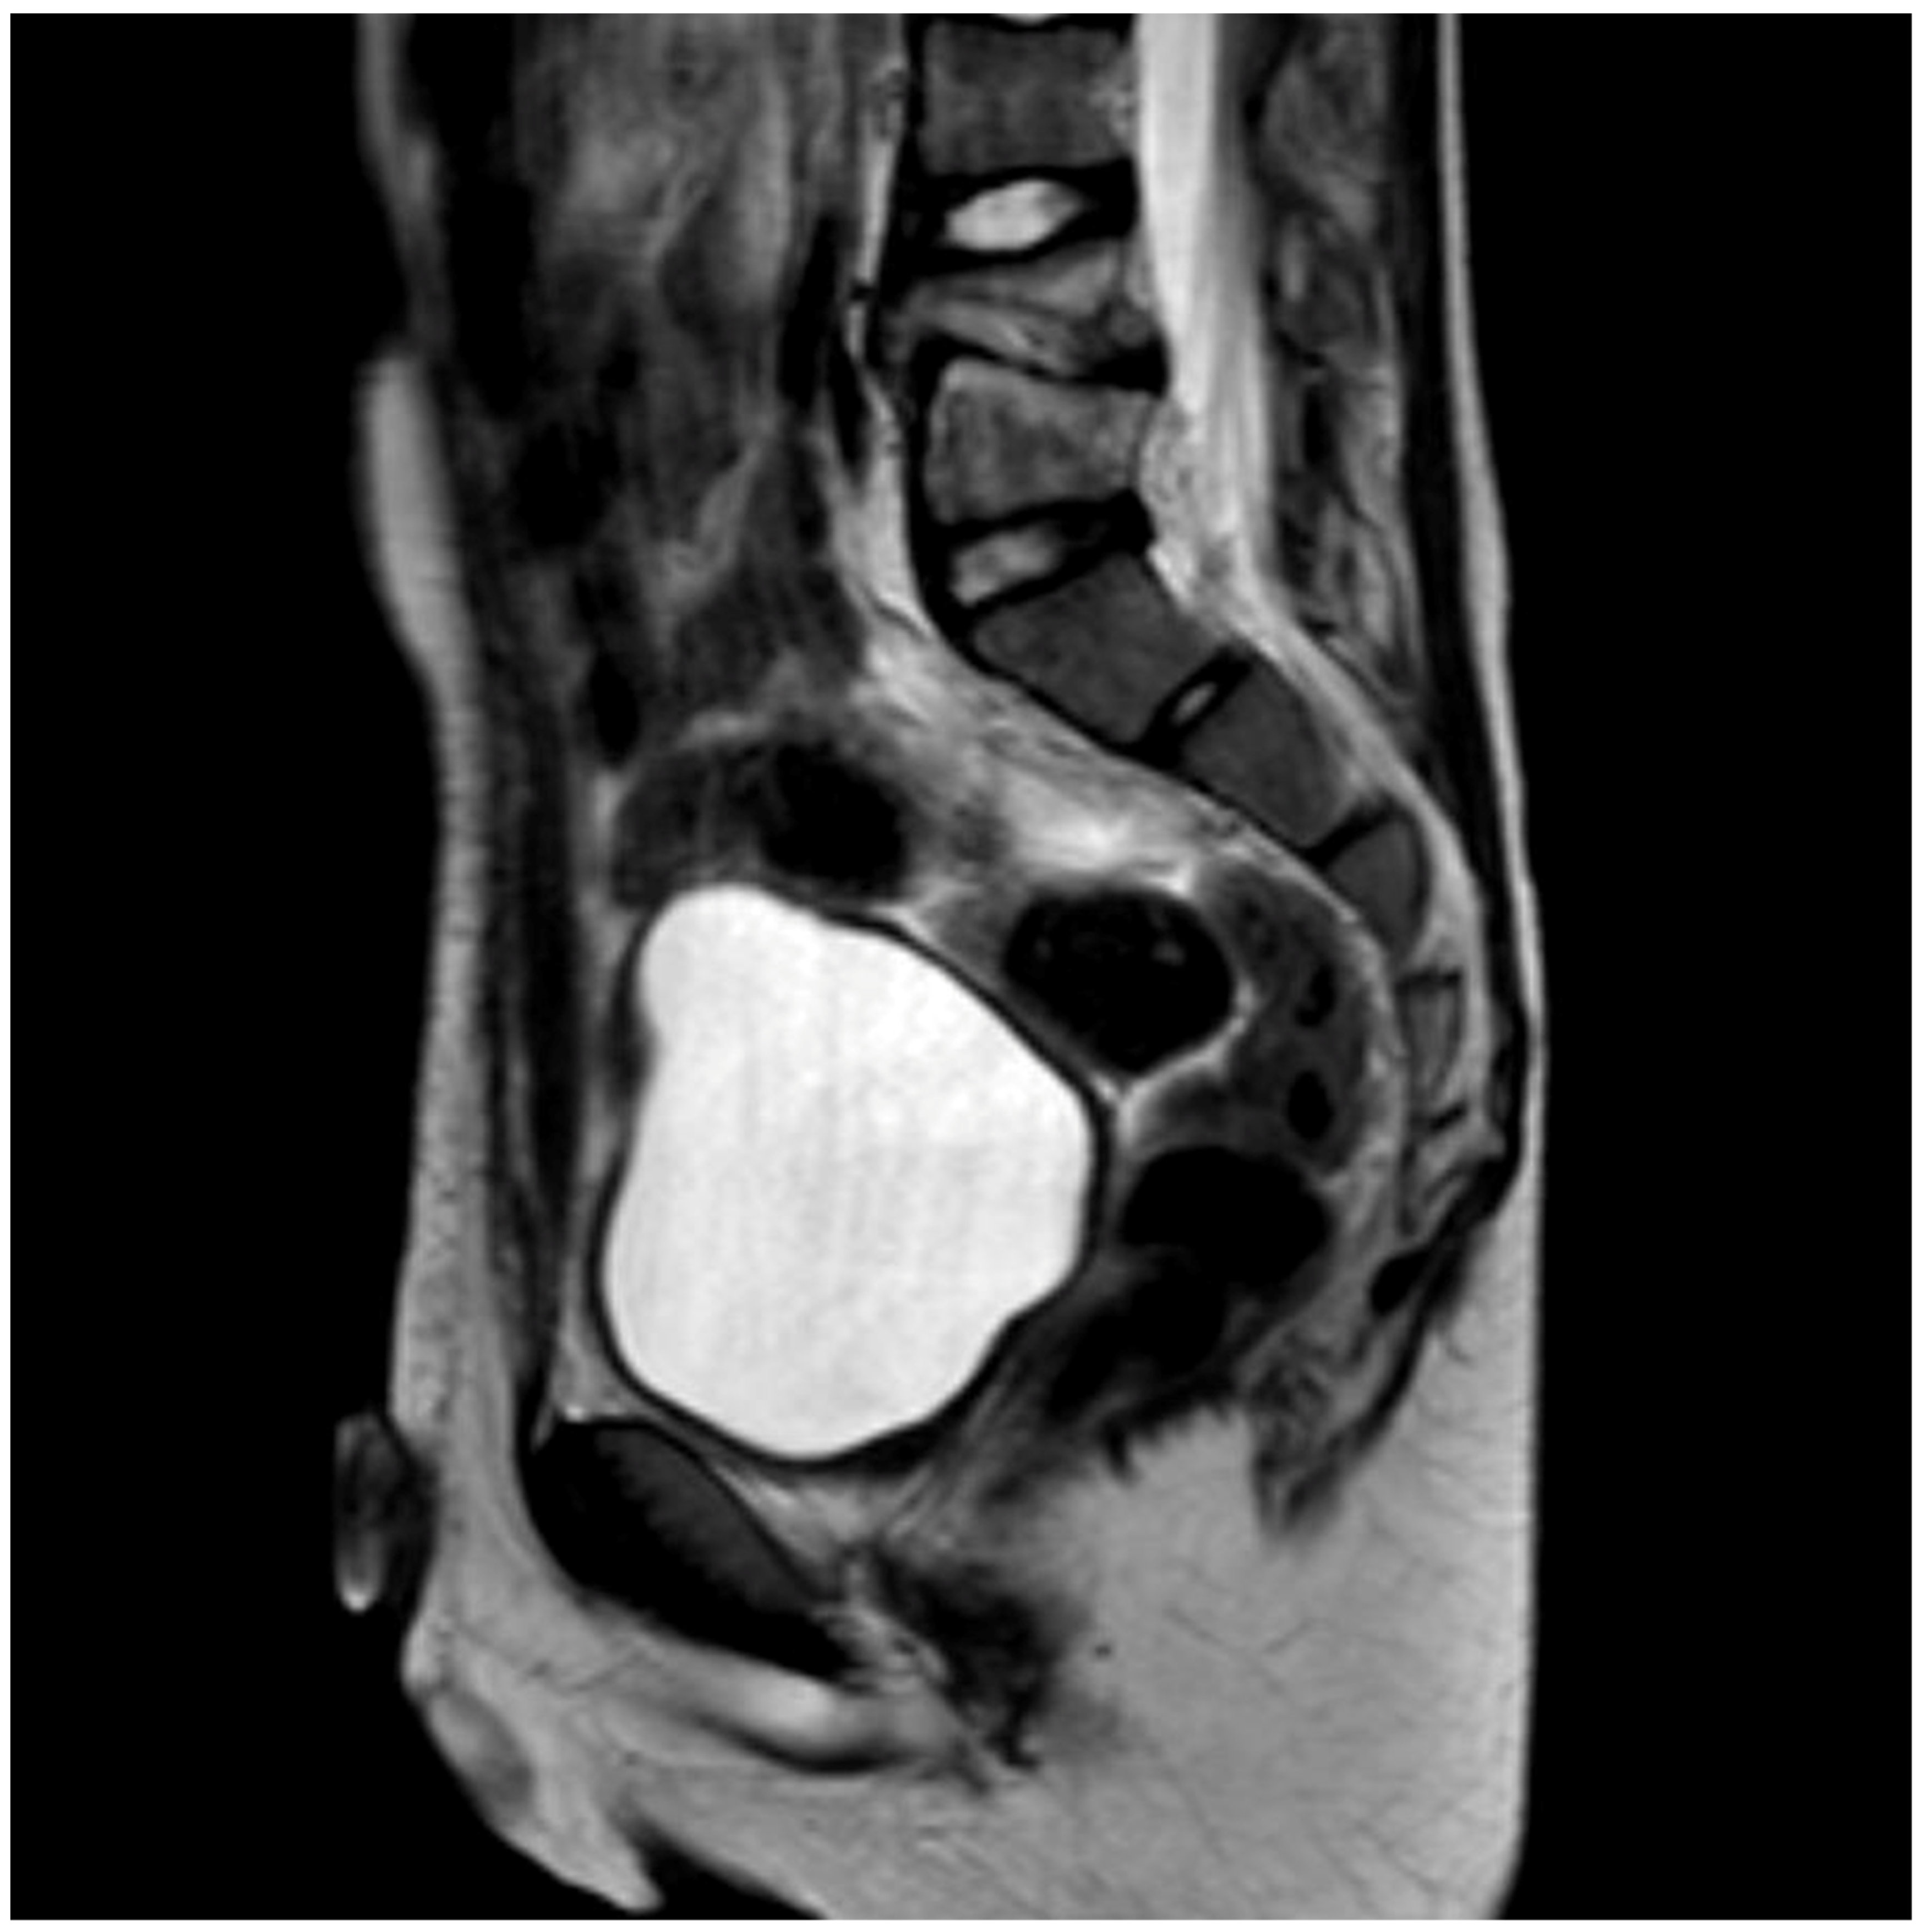

Different methods of imaging were initiated before detecting the final diagnosis of PSD: five children received a sonography of the hips and four patients an X-ray image (Figure 1) while in two cases a CT was performed. The final diagnosis was made by MR-imaging in all cases (Figure 2).

4.5. Imaging

For musculoskeletal pain, the gold standard is plain radiography in two planes as the first imaging method [15]. Thus, the adequate diagnostic tool (MRI of the spine) was not considered immediately. This may be attributed to the pain which was often (50%) located outside of the spine region. Furthermore, a MRI is elaborate to perform as the children often require sedation or anesthesia. Typical MRI alterations are a reduced disc height, disc hypointensity on T1-weighted images, and disc hyperintensity on T2-weighted images. The involved disc shows fluidlike signal intensity in T1- and T2-weighted MRI images.

Figure 2. MRI scan (sagittal view) of the lumbar spine (Pat. No. 10).